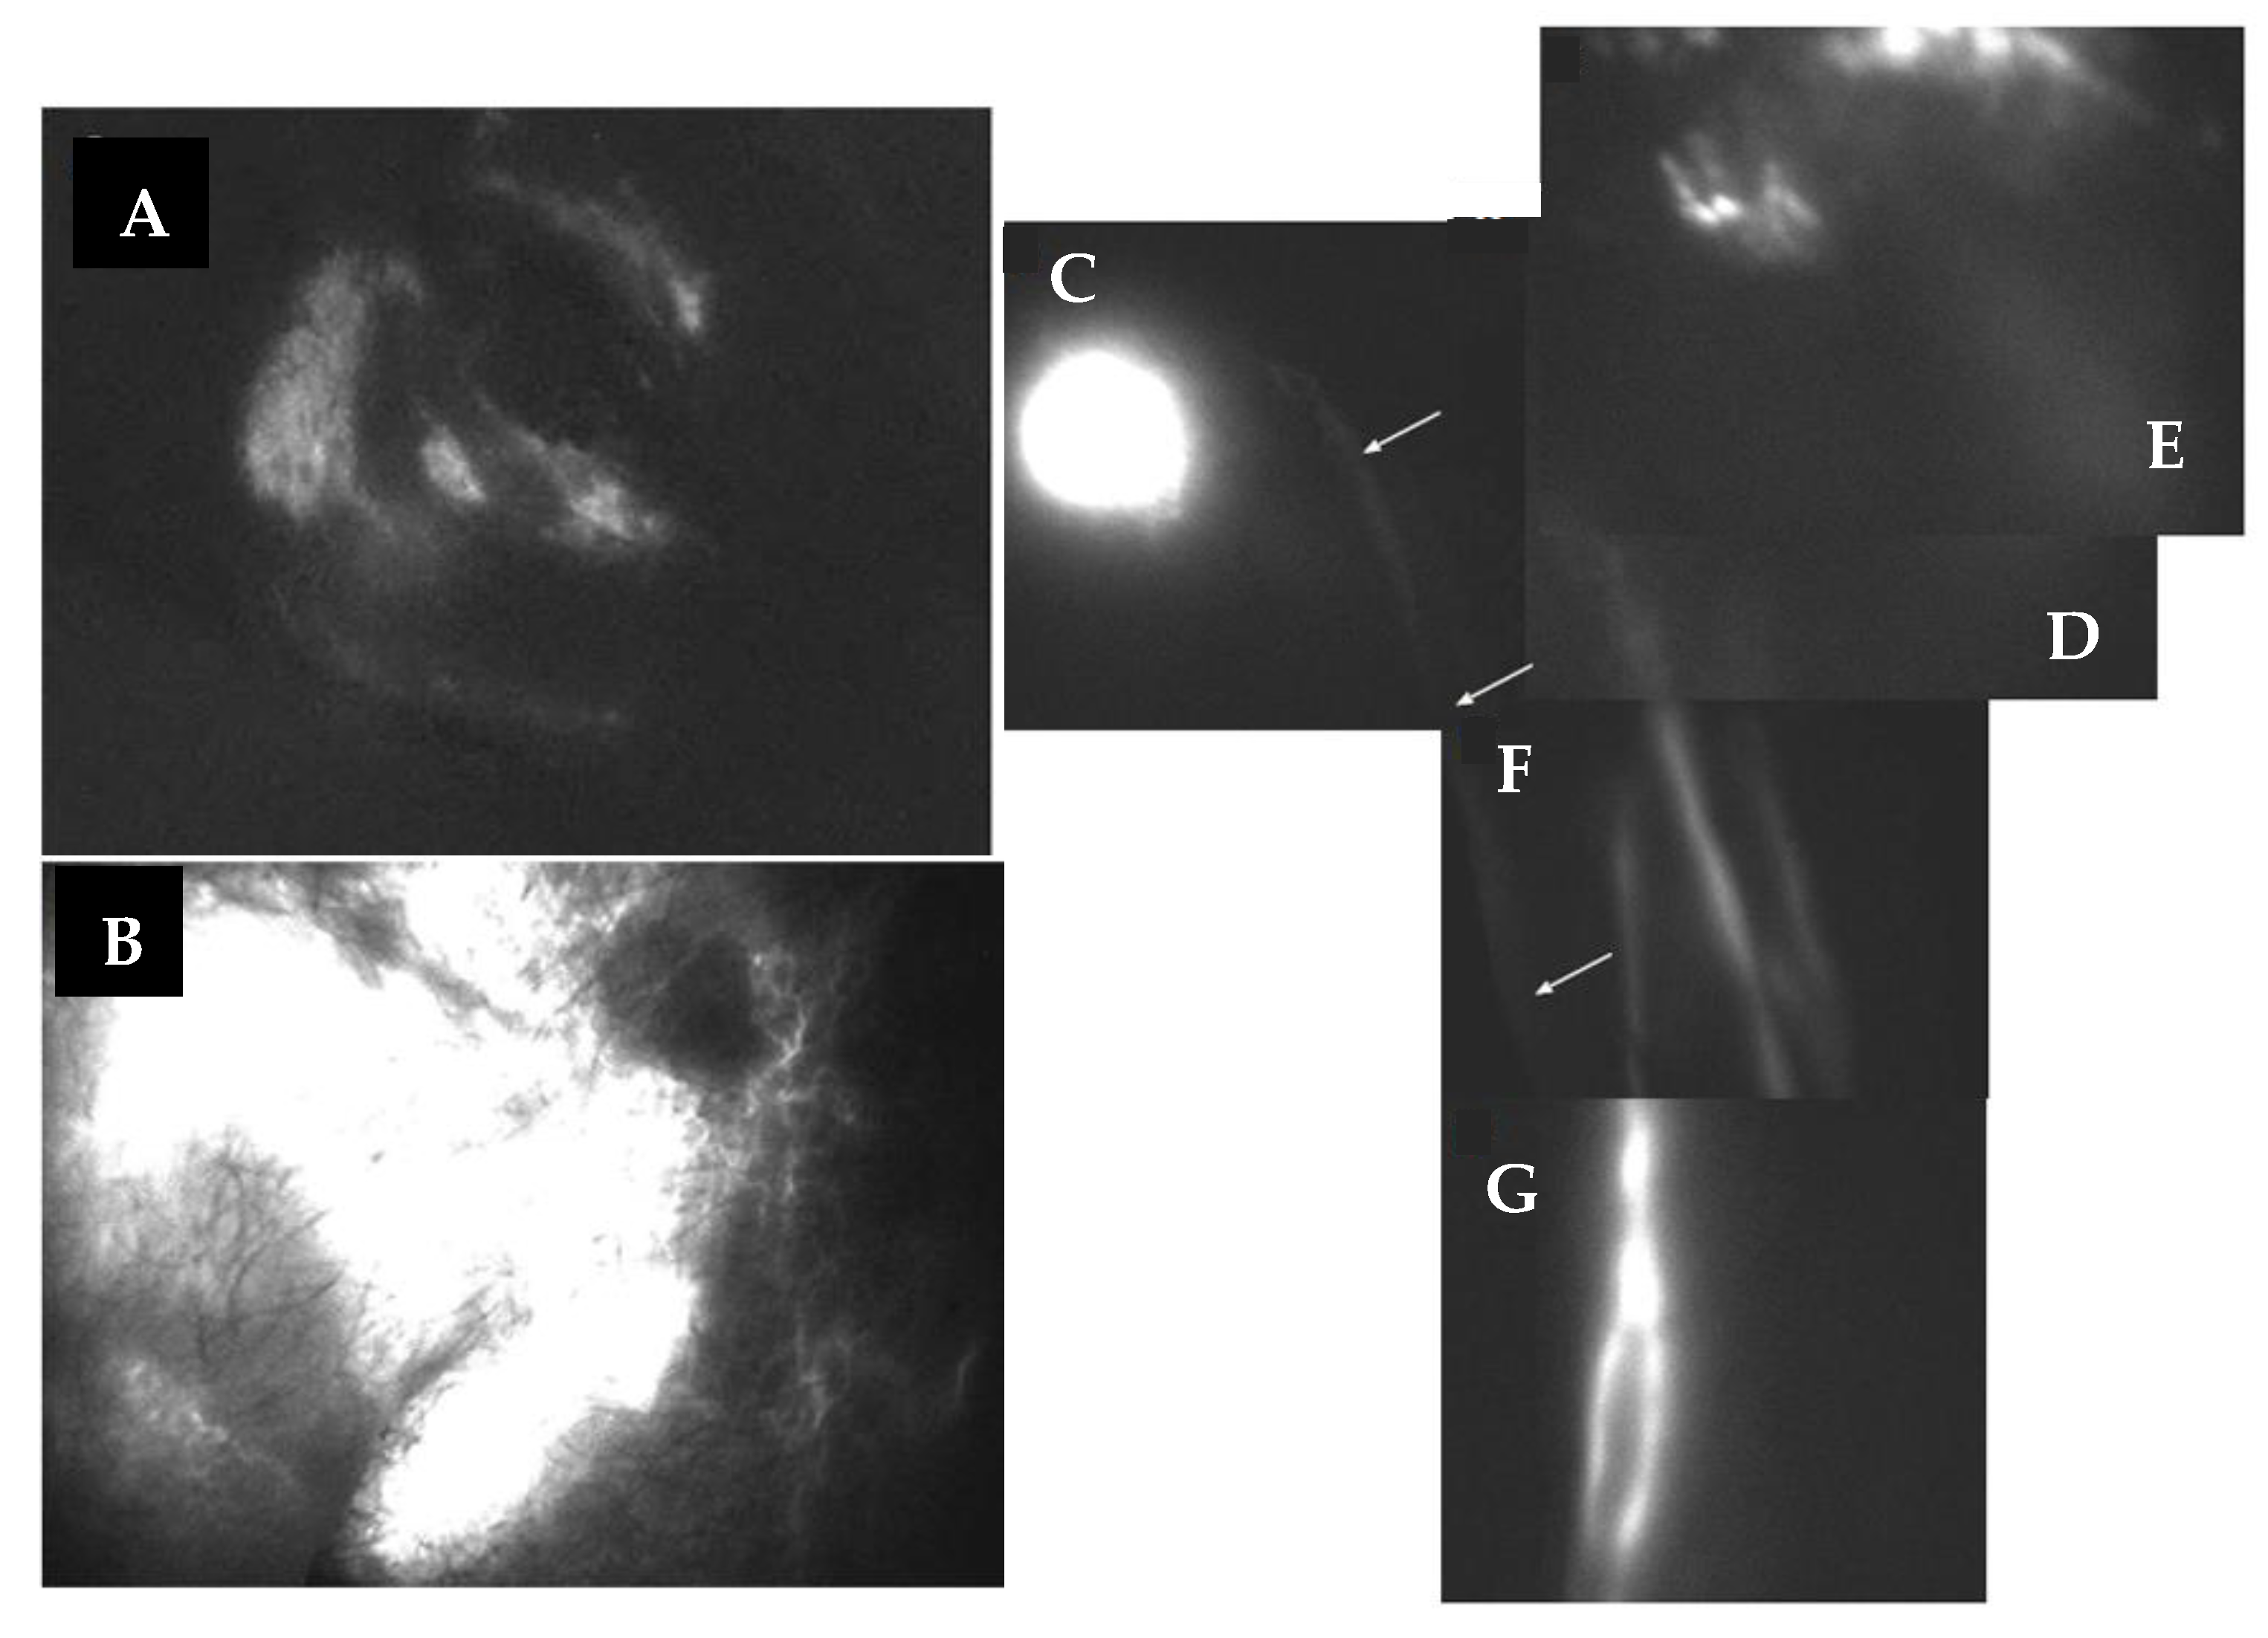

Figure 9. Photodynamic eye (PDE) lymphography shows that, in normal testis (A), the injected dye is canalized into the surrounding lymphatic network and is rapidly drained out of the subcutaneous scrotal tissue. Vice versa, in lymphedematous testis (B), the dye diffusively accumulates in the scrotal subcutaneous tissue because of the impaired lymphatic drainage. Panels C to G show a PDE sequential reconstruction of the pathway, followed by indocyanine injected in the testis (C), and, 1 h after, in the foot of a patient previously suffering of lymphedema of both external genitals and lower limb, after three months after undergoing a lympho-venous shunt of the spermatic cord. Images show that: (1) after injection in the testis, indocyanine is rapidly drained away from the injection site; (2) after injection in the foot, indocyanine flows along lymph vessels from the lower limb (D,E) to be shunted directly into the surgically reconstructed lymphatic route, emptying directly into the spermatic vein (F,G), bypassing the occlusion of the excised pelvic-inguinal lymph-node chain. White arrows help identifying the path of a deep scarcely visible collector.

Lymphedema of male external genitals is often accompanied by unilateral or bilateral chronic swelling of the lower limbs. As such, the microsurgical approach consists of a two-stage treatment: first, genital microsurgery, and, after six months, if needed, lympho-venous shunt of the lower limb (Figure 9).

The results of this approach clearly indicate that the shunt of the spermatic cord in the treatment of genital edema was often accompanied by a significant improvement of the edema of the lower limbs, such as to lead us, after a few cases, to subsequently exclude the two-step surgery. Improvement of limb lymphedema after shunt of the spermatic cord may depend upon the fact that, after excision of inguinal lymph nodes, lymph from lower limbs is shunted through the scrotal and testicular pathways. Similarly, when testicular drainage is restored, edema of the scrotum and penis is also significantly drained, possibly through direct connections between scrotal lymphatics and testicular networks.